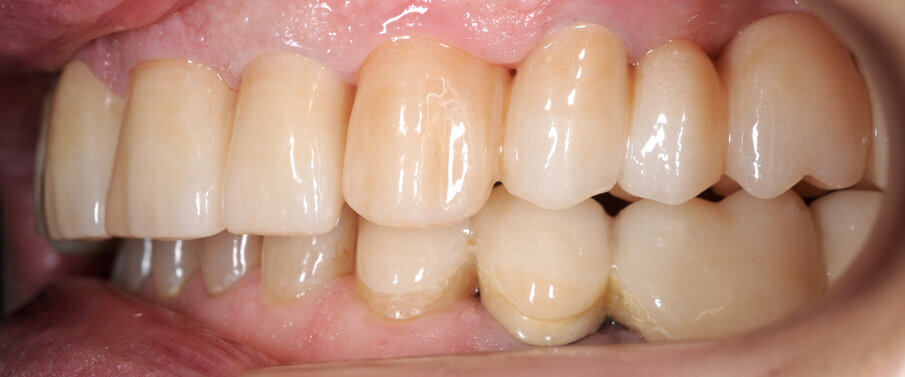

Il fresato ottenuto è poi riportato su articolatore Reference SL – già opportunamente programmato – e viene dall’Odontotecnico competente più precisamente funzionalizzato secondo i criteri della programmazione funzionale sequenziale, evidenziando con cere colorate i rapporti di centrica, le funzioni di mediotrusiva e protrusiva e le protezioni retrusive. I monconi sfilabili consentono la modellazione della sequenzialità mediotrusiva con la guida incisale indicata dalla registrazione axiografica (blu) (Figg. 34-37). La ceratura sequenziale è ora scansita con Sirona InEos X5 su Exocad, ed il modellato viene ricontrollato al CAD per spessori, connessioni e morfologia, e nella regolazione degli offsets per la ripreparazione dei monconi, ed è inviato al CAM per la fresatura dei II provvisori in Bredent breCAM.multicom, un PMMA con microriempitivo ceramico ad alta stabilità, su Dental Plus 5 Axis Milling Machine. La rifinitura dei monconi è seguita da ribasatura dei II provvisori in TRP - previo isolamento di tutte le superfici funzionali - e gli stessi sono poi rifiniti e lucidati. I soli elementi 3.3, 4.2 e 4.3 sono rimodellati in regione incisale con addictions in composito, secondo la morfologia studiata in ceratura. La consegna conferma la buona integrazione dei manufatti dal punto di vista estetico, occlusale, articolare e neuromuscolare, con controllo occlusale conforme al progetto (Figg. 38-42).

Il paziente utilizza questi secondi provvisori per otto settimane, durante le quali conferma la buona integrazione dei restauri e la soddisfacente funzione occlusale. Ciò è verificato con l’esecuzione di una nuova axiografia elettronica che già a due settimane dalla consegna evidenzia una buona risposta muscolare al nuovo design occlusale ed alla nuova postura mandibolare in TRP (Figg. 43-46). Provvediamo infine alle impronte per la costruzione dei manufatti definitivi in Zirconia-ceramica. I modelli sono scansiti in laboratorio con inEos X5 (Dentsply Sirona) su exocad (Figg. 47-49), ed una seconda scansione viene eseguita con i provvisori del Paziente posizionati sui modelli (Figg. 50-52). Il CAD consente di eseguire un matching fra le due scansioni, per cui i secondi provvisori utilizzati in TRP, con funzione occlusale sequenziale già completamente programmata, sono utilizzati per definire le morfologie dentali definitive di tutti gli elementi da restaurare (Figg. 53, 54) secondo il rapporto intermascellare definito (Figg. 55-58). Si esegue quindi fresatura al CAM della protesi definitiva in zirconia (Figg. 59, 60), la stratificazione e finitura ed infine la consegna al Paziente con cementazione in Panavia V5 (Figg. 61-65).